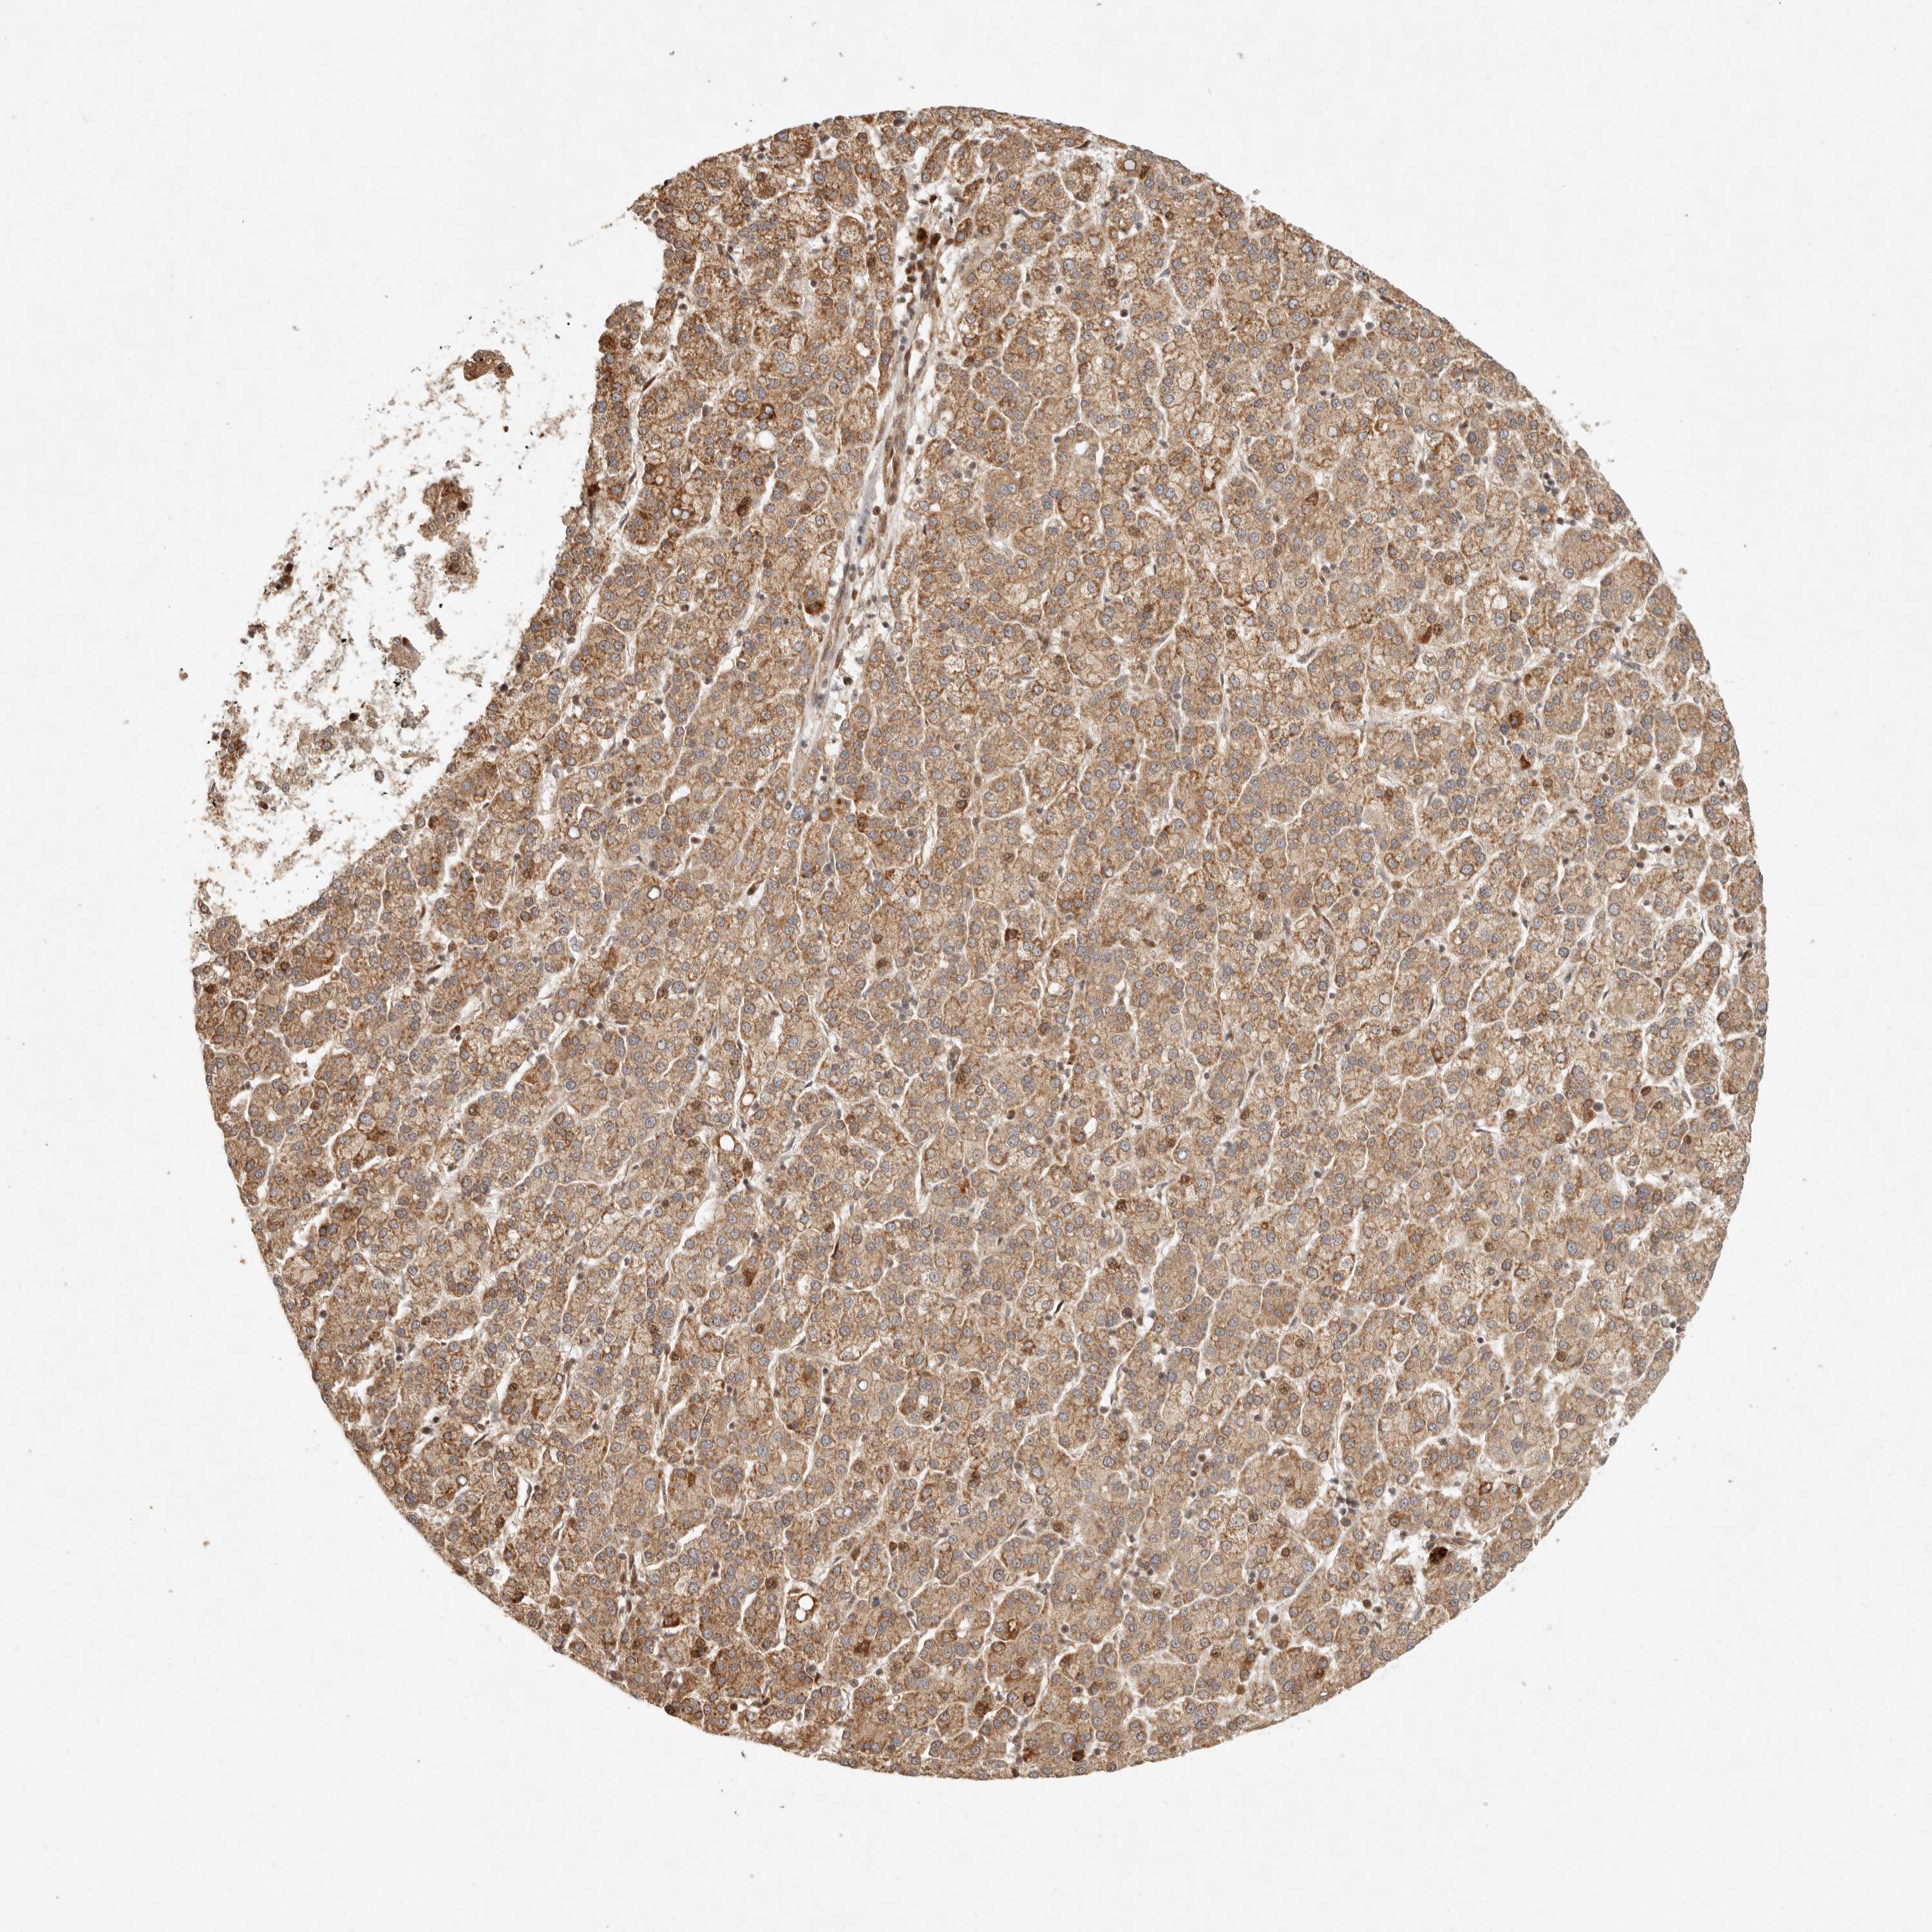

LIVER CANCER - Protein expressioni

A mouse-over function shows sample information and annotation data. Click on an image to view it in a full screen mode. Samples can be filtered based on level of antibody staining by selecting one or several of the following categories: high, medium, low and not detected. The assay and annotation is described here.

Note that samples used for immunohistochemistry by the Human Protein Atlas do not correspond to samples in the TCGA dataset.

Antibody stainingi

Antibody staining in the annotated cell types in the current human tissue is reported as not detected, low, medium, or high, based on conventional immunohistochemistry profiling in selected tissues. This score is based on the combination of the staining intensity and fraction of stained cells.

Each image is clickable and will lead to virtual microscopy that enables deeper exploration of all samples and also displays staining intensity scores, fraction scores and subcellular localization as well as patient and tissue information for each sample.

Antibody HPA024770

Antibody HPA027115

Staining

High

Medium

Low

Not detected

Intensity

Strong

Moderate

Weak

Negative

Quantity

>75%

75%-25%

<25%

None

Location

Nuclear

Cytoplasmic/membranous

Cytoplasmic/membranous,nuclear

Cholangiocarcinoma

Carcinoma, Hepatocellular, NOS